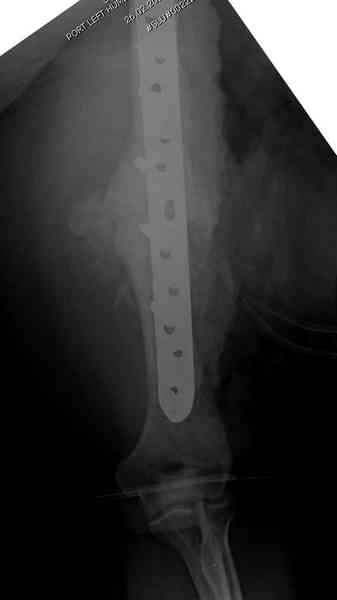

Помогите, пожалуйста, определиться с тактикой!Поступил больной с ложным суставом плечевой кости... Перелом был 2 года назад. Лечился в аппарате 8 месяцев, консолидации не произошло. В феврале 2007 выполнена костная аутопластика, фиксация пластиной (на базе одной из ИК). Сейчас сохраняется ложный сустав, плечо укорочено на 3 см, контрактура обоих смежных суставов, атрофия мышц плеча и плечевого пояса справа. Явлений остеомиелита не отмечалось. Больной - осужденный, сидеть ему до 2012 года.

Уважаемая Татьяна,

Как видно из выступлений коллег, способы фиксации

ложного сустава плеча могут быть различными, кто-то предпочитает аппаратом Илизарова (Соломин), пластинами (Волна) или интрамедуллярным гвоздем (Челноков).

Когда разбирался случай на сайте, и у нас была больная с похожей патологией, ложный сустав после поперечного перелома, леченного год назад где-то и кем-то в другом месте.

Мы не стали делать провокационный метод, который

предложил Корнеев для лечения - применение анаболических стероидов - ретаболила, из-за его бессмысленности, также не согласились с его теорией, что любая операция заблокирует суставы, а наоборот, провели жесткую фиксацию пластиной для раннего восстановления.

Первичную пластину убрали недели 6 назад из переднего оригинального доступа, и из-за подозрительности тканей вокруг пластины, решили провести реконструкцию поэтапно.

После промывки и дебридмента для уверенности уложили антибиотический цемент. Культура из раны в последующем была отрицательная.

Хотя сам не стороннник применения более массивных

имплантов для плеча, но для этого случая сделали

исключение. На снимке 4А диаметр мягких ткани около 20 см, при весе больной более 135 кг, и также выступление Андрея Волны подстегнуло к применению более массивной 4.5 мм локинг пластины.